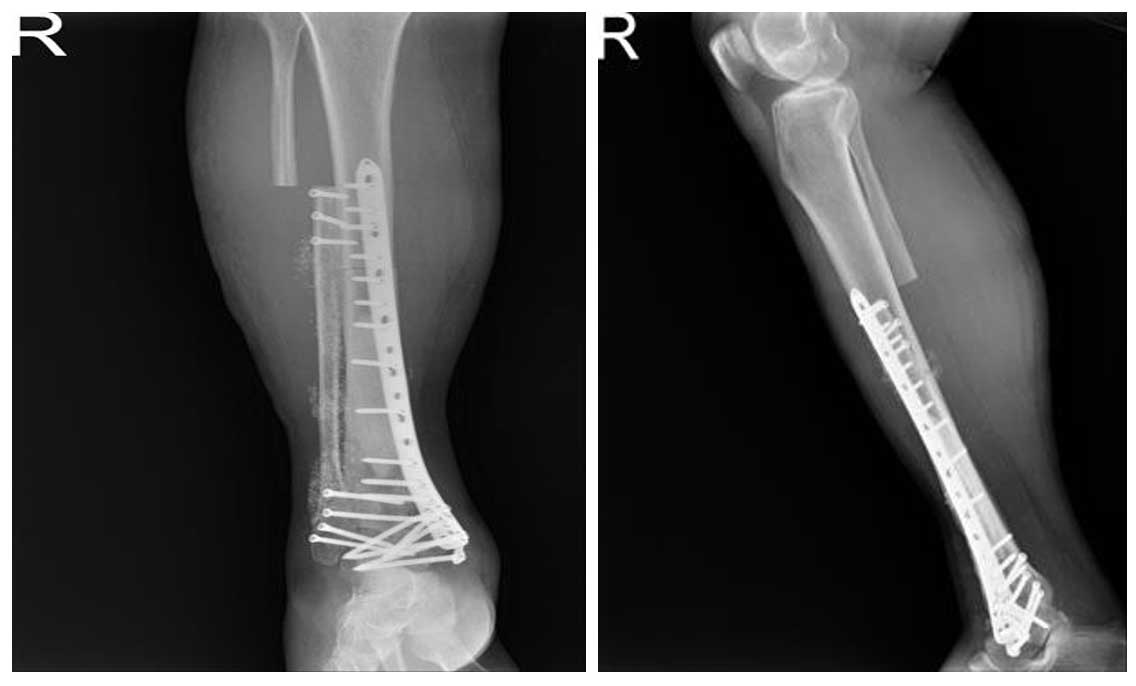

Ameliyat Esnası: Geri kazanılan kemiğin yerine yerleştirildikten sonra plak ile fiksasyonu ve yaranın kapatılması görülmekte.

Ameliyat Sonrası: Röntgende ayak bileği artrodezi ile birlikte fibulanın fiksasyonu görülmekte.